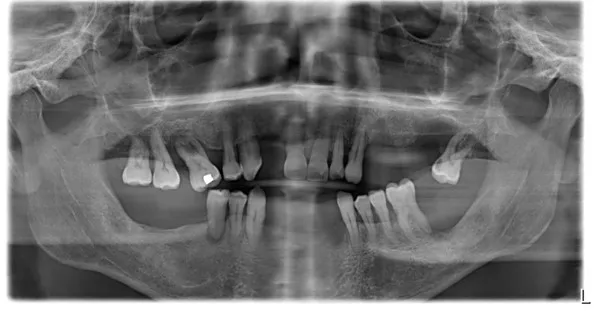

1. OPG showing peri-dental bone involvement and sufficient residual bone for implant placement.

The proposed treatment plan includes the extraction of all remaining teeth, the immediate placement of 6 implants in the upper jaw, and 4 implants in the lower jaw. Due to unfavorable periodontal conditions, the use of tissue-level implants is necessary. Their design promotes the formation of an epithelio-connective barrier above each implant, ensuring natural protection of peri-implant bone tissues.